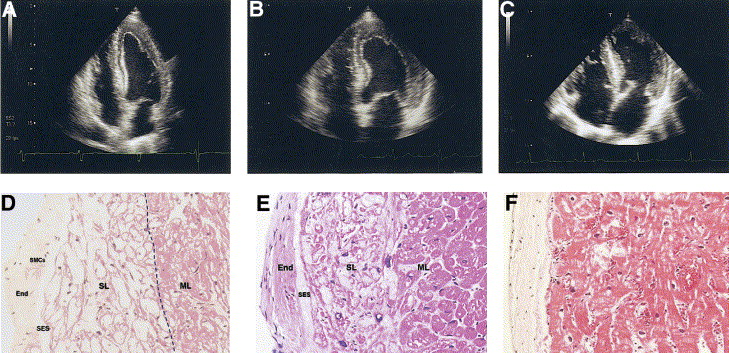

- Two-dimensional echocardiography in 4CH-apical view and LV endomyocardial biopsy from two patients with AFD (A,D and B, E) and a patient with sarcomeric HCM (C,F). Comparison of the three echocardiographic frames reveals the presence of a binary appear